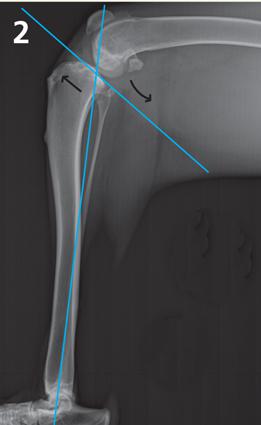

During weight bearing, the femur slides down the tibial plateau. The (ACL) stops this downward slope, therefore, is under constant tension during weight bearing. It is this biomechanical problem that leads to most ACL ruptures and may cause older repair techniques to fail.